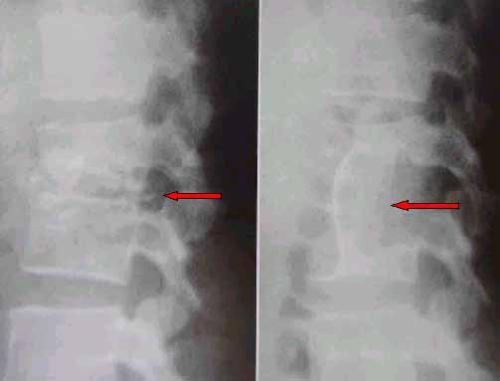

腰椎结核一般在发病时,患者会出现低热、疲倦、消瘦、盗汗、食欲不振与贫血等全身症状。儿童常有夜啼,呆滞或性情急躁等。随着病情的发展,不少患者会出现疼痛加重呈放射性疼痛,沿神经传播到下肢、肩部、臀部等。腰椎结核发病严重,椎体出现破坏,患者会出现畸形,脊柱多有后凸,患者不能弯腰、也不能直腰行走。

湖北夏小中医院专家表示:腰椎结核截瘫是其严重的并发症。有资料显示:它占了所有脊椎结核的10%~20%。白求恩医科大学报导950例脊柱结核,其中有36.8%并发截瘫,可见腰椎结核合并截瘫,相当多见,是危害我国人民健康的常见疾病,治疗上防止截瘫已刻不容缓。>>>腰椎结核好治吗?

腰椎结核会截瘫吗?不及时的治疗会让患者产生截瘫的危险,因此我院专家提醒:腰椎结核患者赶紧抓紧时间治疗,不要耽误佳的治疗时机。>>>请医生帮我看一看,制定佳治疗方案